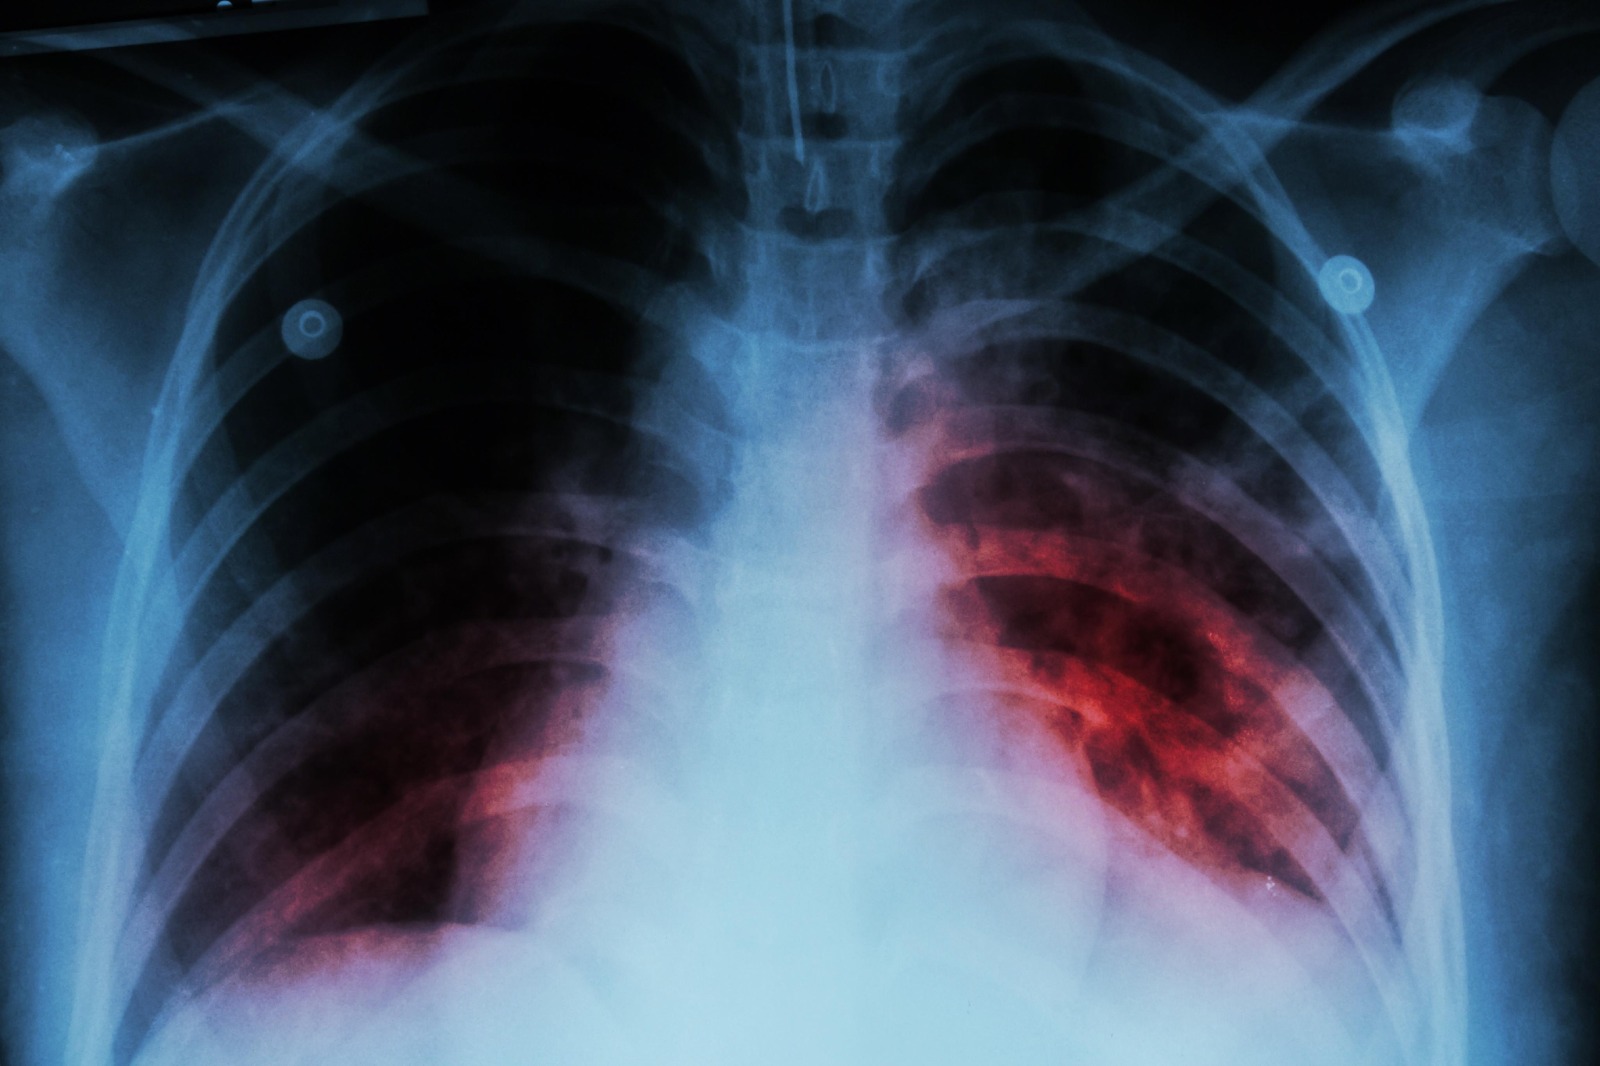

Piedras Negras, Coahuila.- En lo concerniente a las detecciones realizadas por parte del área de Micobacteriosis de la Jurisdicción Sanitaria para encontrar casos de tuberculosis, fueron 475 estudios, de los cuales 70 fueron positivos, mientras que por parte de otras instituciones se registraron 122 diagnósticos, lo que da un total de 192 pacientes que padecieron la enfermedad durante 2025.

Sallory Casas, responsable del área en mención, destacó que la mayor parte de los casos positivos son nuevos, siendo pocos los reincidentes, todos los pacientes recibieron su tratamiento de manera gratuita por espacio de seis meses para casos de primera vez, mientras que los que recaen llevan uno que dura de 9 a 12 meses.

La responsable del área recordó que toda aquella persona con tos constante por espacio de más de dos semanas es candidata a practicarse el estudio, el cual es gratuito en la Jurisdicción Sanitaria.